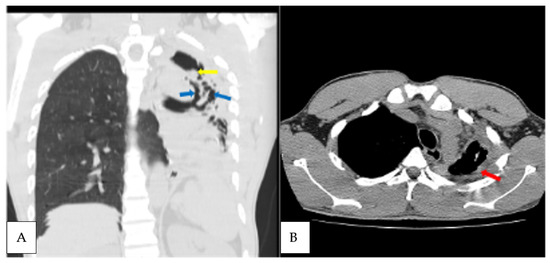

| 49 | M | Cough, dyspnoea, weight loss | Positive | A. fumigatus | Cavities, fungal ball, pleural thickening adjacent cavity, pericavitary fibrosis, bronchiectasis | 46, 14, 23 |